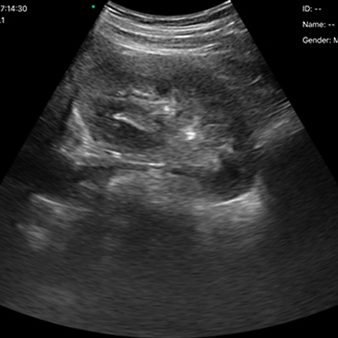

El escáner de ultrasonido portátil de doble sonda es una solución avanzada diseñada para ofrecer máxima versatilidad clínica en un solo dispositivo. Gracias a su tecnología integrada, combina tres modos de escaneo —convexo, lineal y phased array— permitiendo evaluar estructuras profundas, tejidos superficiales y realizar estudios cardíacos con alta precisión. Esta integración reduce significativamente los costos al reemplazar la necesidad de adquirir múltiples sondas por separado.

- Un solo escáner escanea todo el cuerpo, incluso el cardíaco.